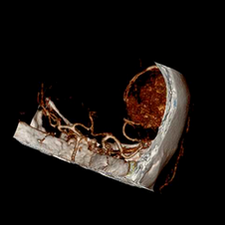

标题: CT25808:男,48岁,头痛多年,近段时间头痛加重伴步态不稳 [打印本页]

标题: CT25808:男,48岁,头痛多年,近段时间头痛加重伴步态不稳

平扫:右颞顶叶病灶呈等低密度伴大面积水肿,脑室受压变形。增强:病灶显著强化。考虑淋巴瘤或黑色素瘤。